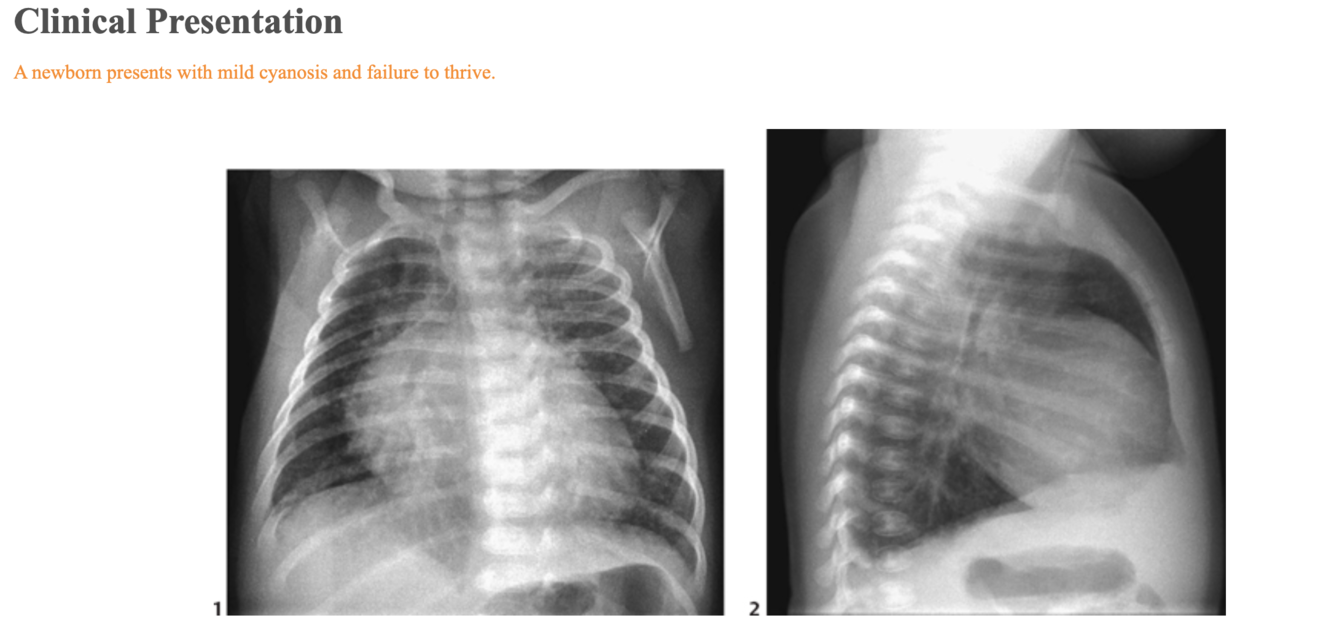

Radiologic Findings

The frontal chest radiograph (Fig. 46A1) shows a moderately enlarged heart with an egg-on-side configuration and increased pulmonary vascularity. The superior mediastinum is narrow because of thymic hypoplasia. Note that the anterior upper mediastinum is empty in lateral view (Fig. 46A2).

Figure 46B Schematic diagram of four types of truncus arteriosus as described by Collet and Edwards.

Diagnosis

Truncus arteriosus with DiGeorge syndrome

Differential Diagnosis

Egg-on-side appearance:

Complete transposition of the great arteries: pulmonary vascularity, variable

Pulmonary atresia with intact ventricular septum: diminished pulmonary vascularity

Truncus arteriosus: increased pulmonary vascularity

Boot-shaped heart: In truncus arteriosis the heart may also be boot shaped, but this is less common.

Tetralogy of Fallot: normal heart size and diminished pulmonary vascularity

Pulmonary atresia with ventricular septal defect: normal heart size with diminished pulmonary vascularity or enlarged heart with increased pulmonary vascularity

Truncus arteriosus: moderate cardiomegaly with increased pulmonary vascularity

Narrow superior mediastinum:

Complete transposition of the great arteries with postnatal regression of the thymus

Truncus arteriosus with thymic hypoplasia in association with DiGeorge syndrome or postnatal regression of the thymus

Discussion

Clinical Findings

Most patients with truncus are recognized as having congenital heart disease during the neonatal period. During the first few weeks of life, persistence of increased pulmonary vascular resistance results in mild cyanosis with little evidence of heart failure. As the pulmonary vascular resistance decreases, cyanosis may disappear and be replaced by signs of congestive heart failure. When the truncal valve is severely regurgitant, the signs of congestive heart failure may manifest immediately after birth. Generally, the heart is overactive, and a pansystolic murmur is heard at the left precordium. Microdeletion of chromosome 22q11 is seen in ~40% of patients with truncus, and patients with this deletion include DiGeorge and velocardiofacial syndrome cases.